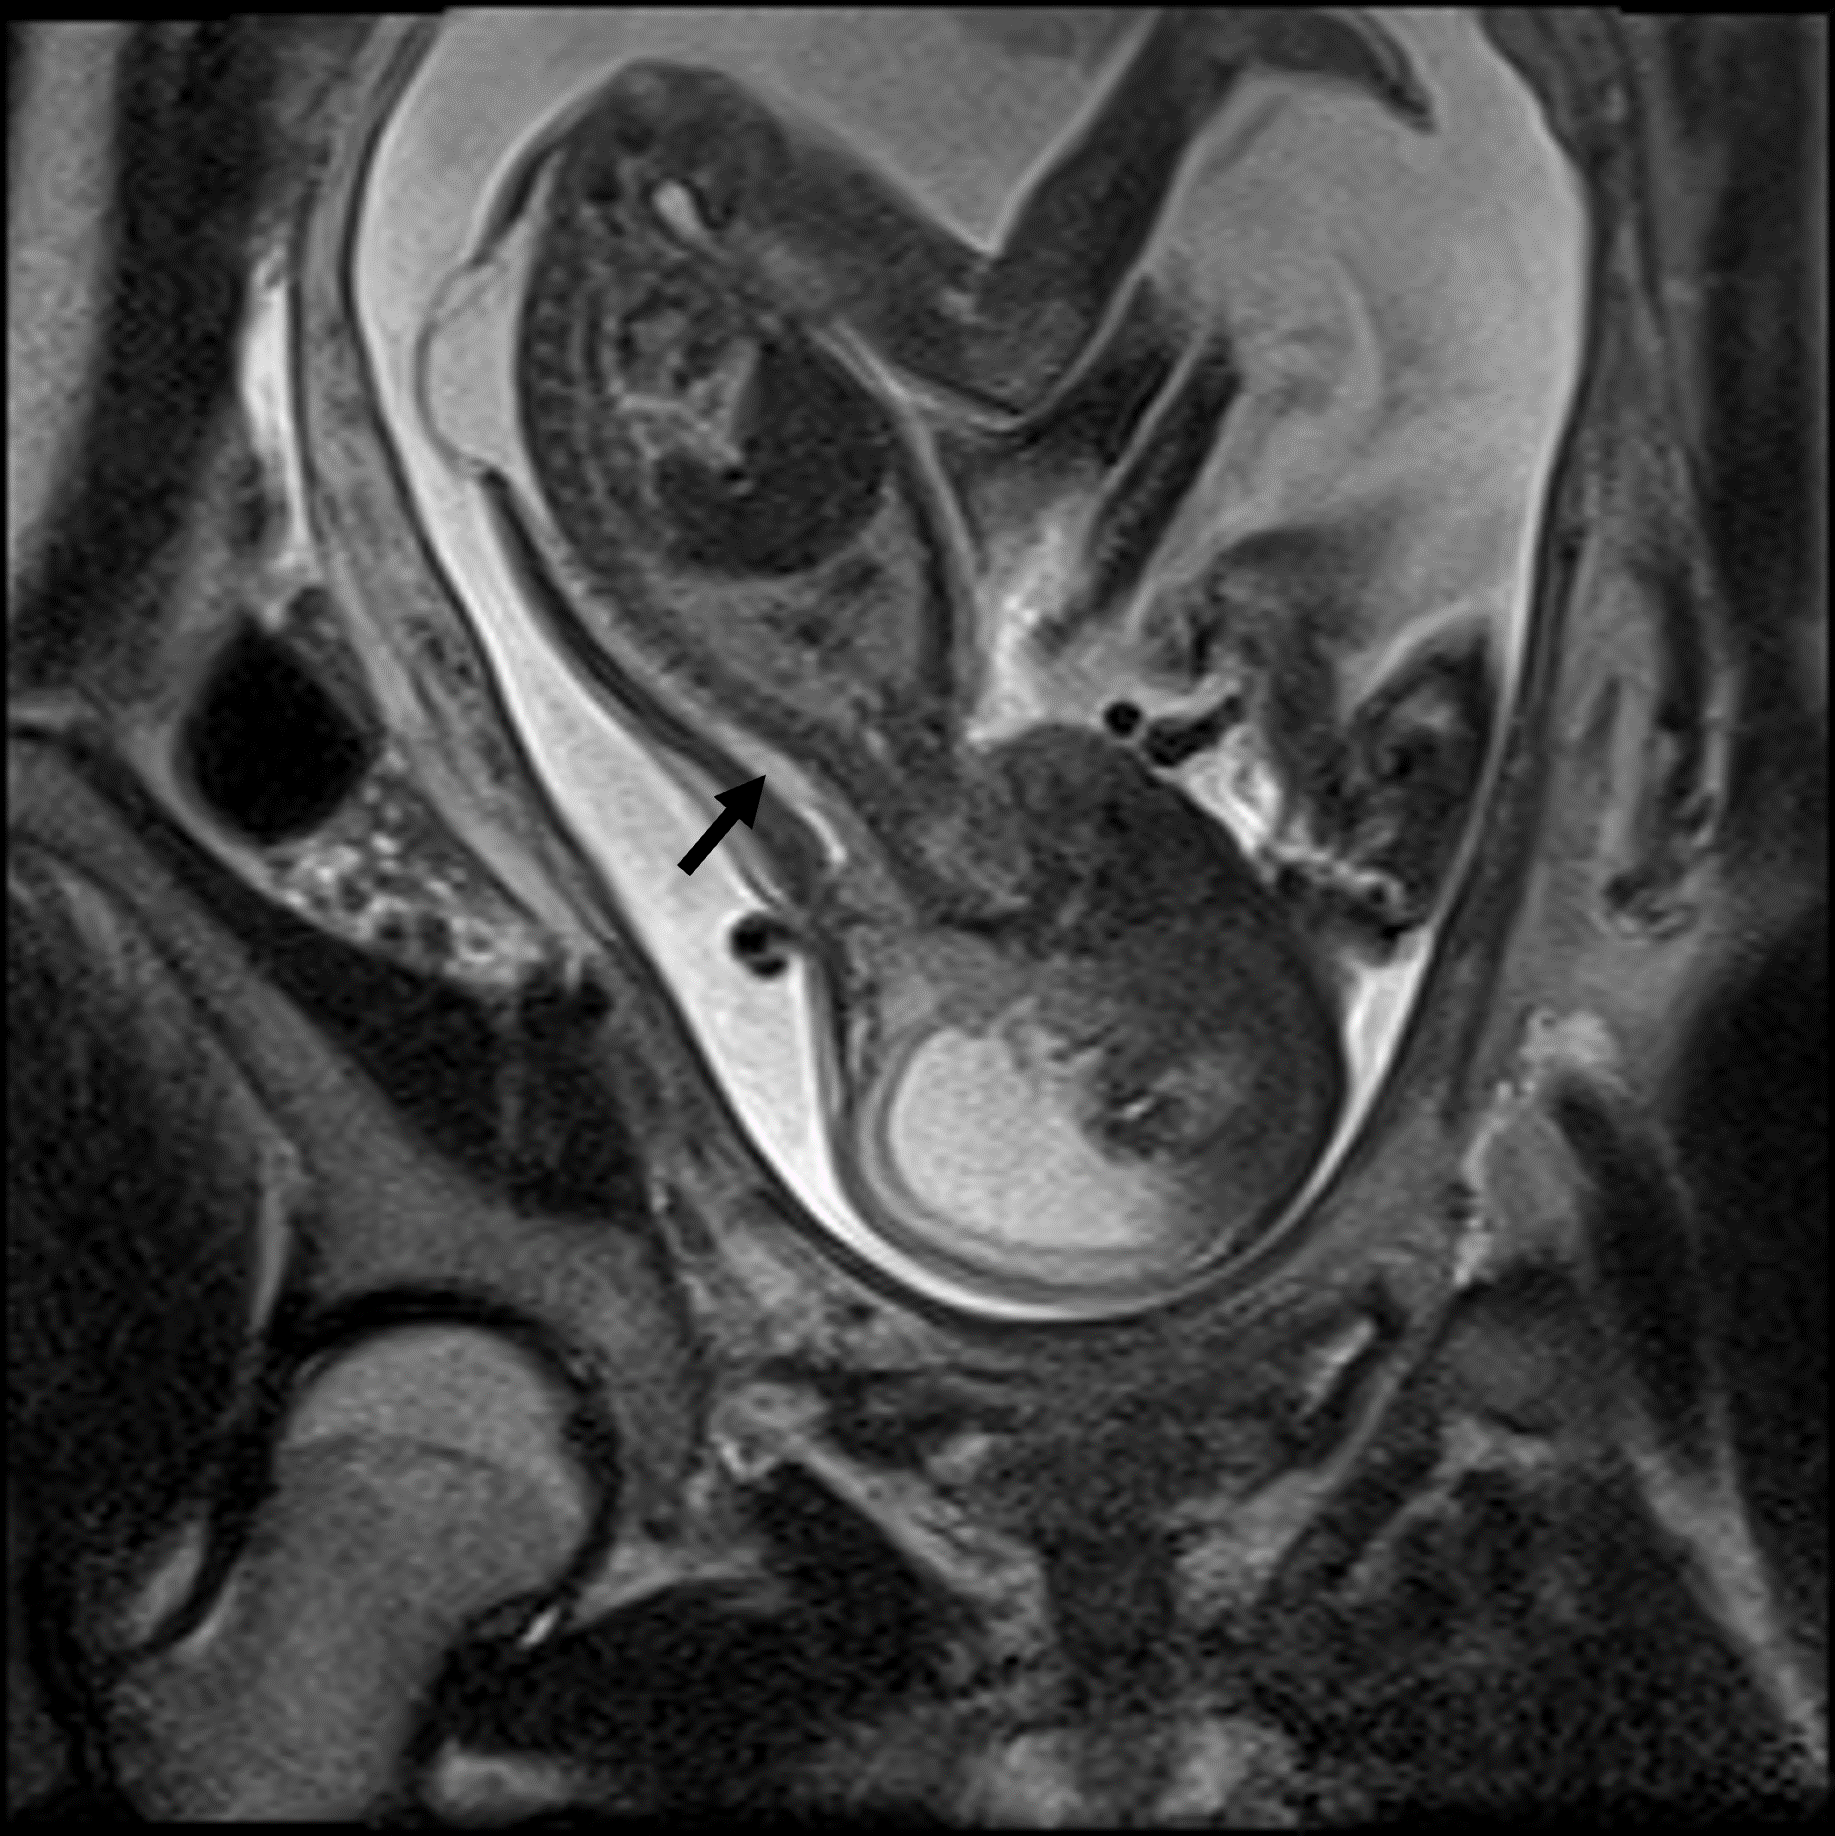

Das fetale MRT (Magnetresonanztomographie) ist ein strahlungsfreies Verfahren, mit dem wir Organe und Strukturen Ihres ungeborenen Kindes besonders detailreich darstellen. Es ergänzt die pränatale Ultraschall-Diagnostik und hilft, Fragestellungen präzise zu klären und die weitere Betreuung zu planen.

- Abklärung von Auffälligkeiten im Ultraschall, z. B. Gehirn, Wirbelsäule, Lunge, Bauchorgane

- Beurteilung von Organreife und Entwicklung, wenn die Sicht im Ultraschall eingeschränkt ist (z. B. mütterlicher Body-Mass-Index, Lage des Kindes)

- Therapieplanung vor/nach intrauterinen Eingriffen oder für die Geburt in einem spezialisierten Zentrum

- Auswertung: Die Bilder werden von unseren Spezialistinnen und Spezialisten ausgewertet und im interdisziplinären Board aus Pränatalmedizinern, Neuroradiologen, Pädiatern und Chirurgen besprochen. Der Befund wird an Ihre/ Ihren betreuende Ärztin/Arzt übermittelt und mit Ihnen besprochen.

Unsere Neuroradiologen arbeiten eng mit Pränatalmedizinern, Neonatologen, Pädiatern und Chirurgen zusammen. Modernste Geräte und spezialisierte Protokolle sorgen für hohe Bildqualität – auch bei kindlichen Bewegungen.